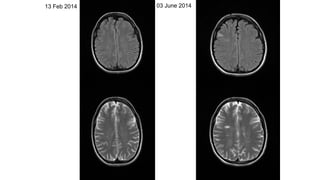

JS – 28 year old female -February 2014 – paraesthesia of upper limbs and thorax,

resolved after 4 weeks,stable since, ANA +ve and lupus anticoagulant, Raynaud’s phenomenon

13 Feb 2014 03 June 2014

13 Feb 201403 June 2014